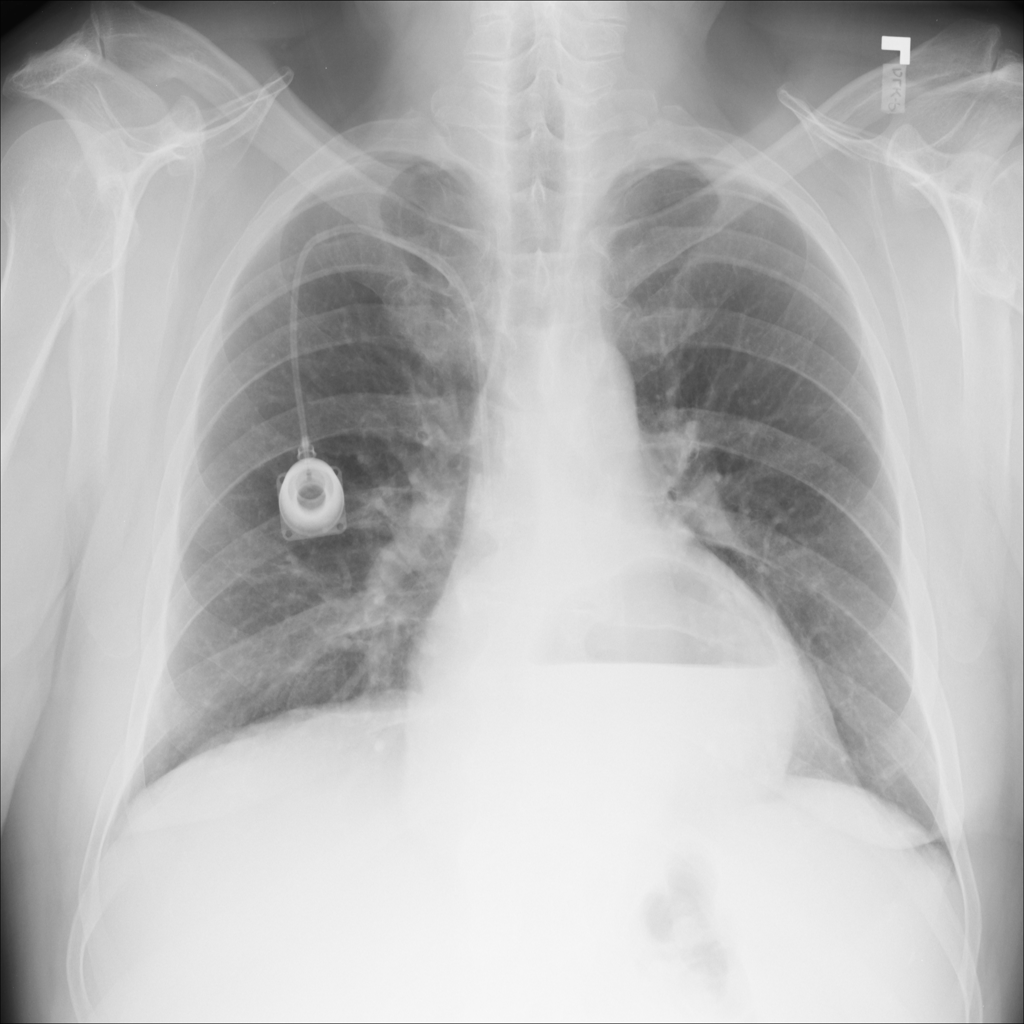

PAT-0ABD · IMG-000Hernia

PAT-0ABD · IMG-000

PA